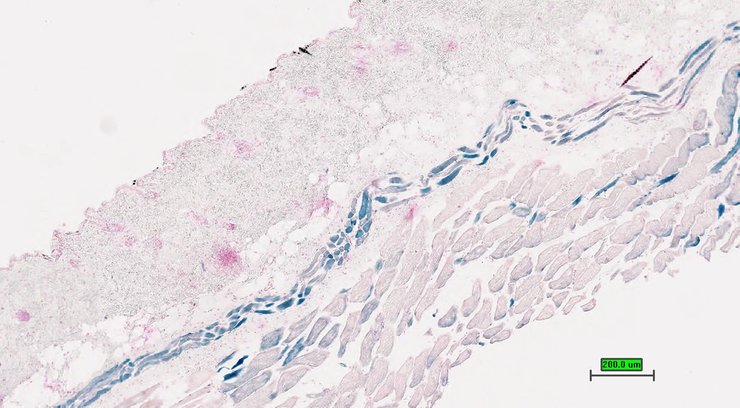

TS28: skin Present UC Davis_1873314

Specimen UC Davis_1873315: postnatal adult; Cldn18tm1.1(KOMP)Vlcg/Cldn18+ (more )

Structure Level Pattern Image Note

TS28: skin Present UC Davis_1873315